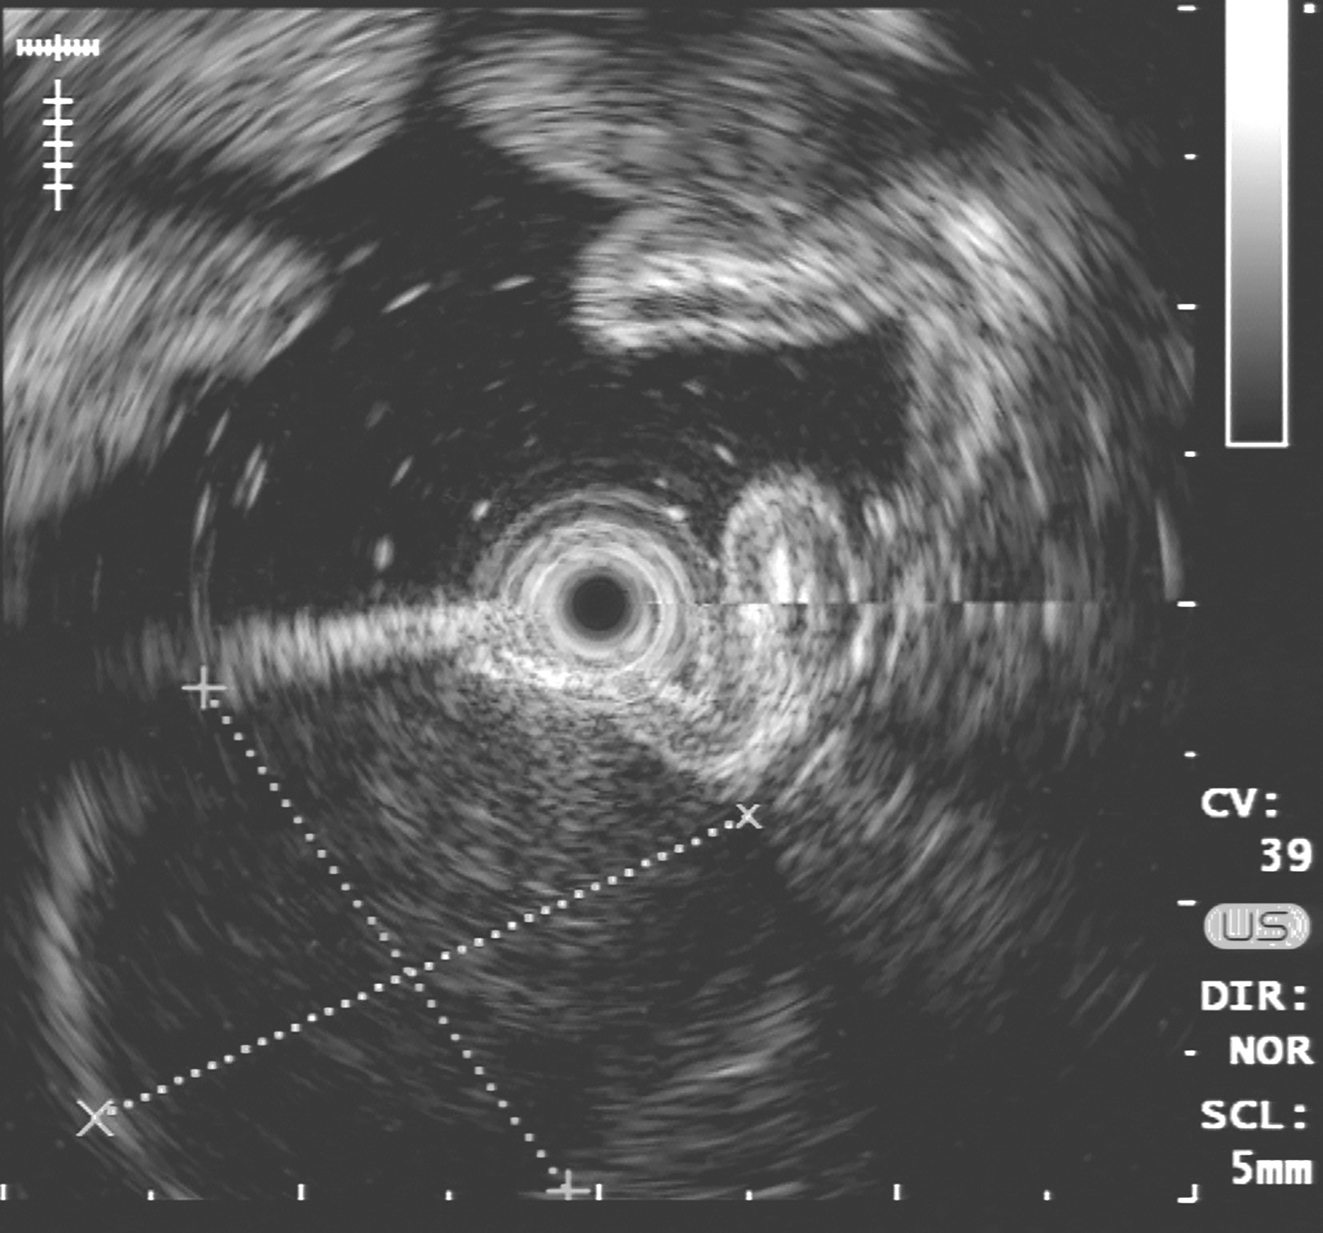

超声胃镜:胃体上段后壁可见一隆起病灶,隆起处为一低回声团块,内回声尚均匀,起源于第四层,向腔内外突出(图1)。

图1 超声内镜提示胃体隆起灶起源于第四层,向腔内外突出